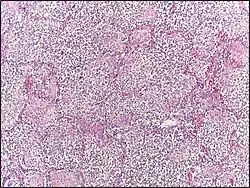

- Red hepatization or consolidation: Vascular congestion persists, with extravasation of red blood cells into alveolar spaces, along with increased numbers of neutrophils and fibrin. The filling of air spaces by the exudate leads to a gross appearance of solidification, or consolidation, of the alveolar parenchyma. This appearance has been likened to that of the liver, hence the term "hepatization".

- Grey hepatization: Red blood cells disintegrate, with the persistence of neutrophils and fibrin. The alveoli still appear consolidated, but grossly the color is paler and the cut surface is drier. This is when death typically occurs in severe cases.